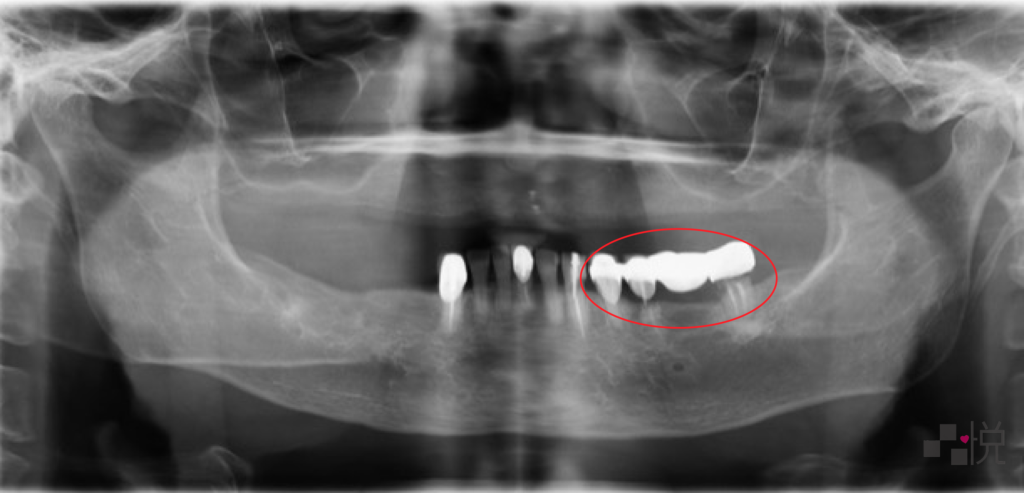

此圖為下顎活動假牙剛完成一年多的X光片,陳阿姨左側腫痛不已,原來是當時沒發現左側牙橋下的蛀牙,為了治療蛀牙,剛做好一年多的活動假牙也得重新製作,金錢跟時間都浪費了。